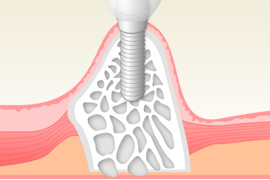

横の歯に負担がかからないインプラント治療

症状

- 1

- 横の歯に負担をかからないので、自分の歯が残ります。

- 2

- 天然歯のように顎には生理的刺激がいくた、顎の骨がやせない。

- 3

- もしインプラントがダメになっても骨は再生可能なので1本だけの治療で済みます。

そしてなにより - 4

- 噛みごたえのある食生活は幸福感を高くします。